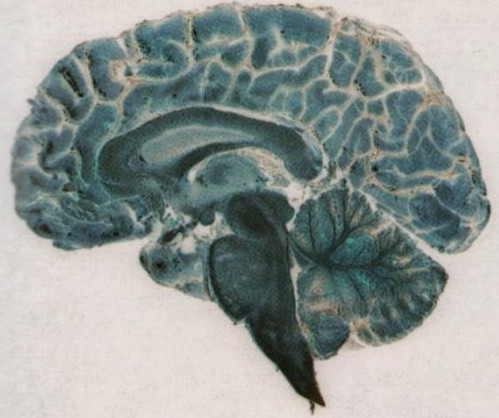

Melatonin in the Central Nervous System (CNS)

The Hippocampus

Melatonin and the Hippocampus